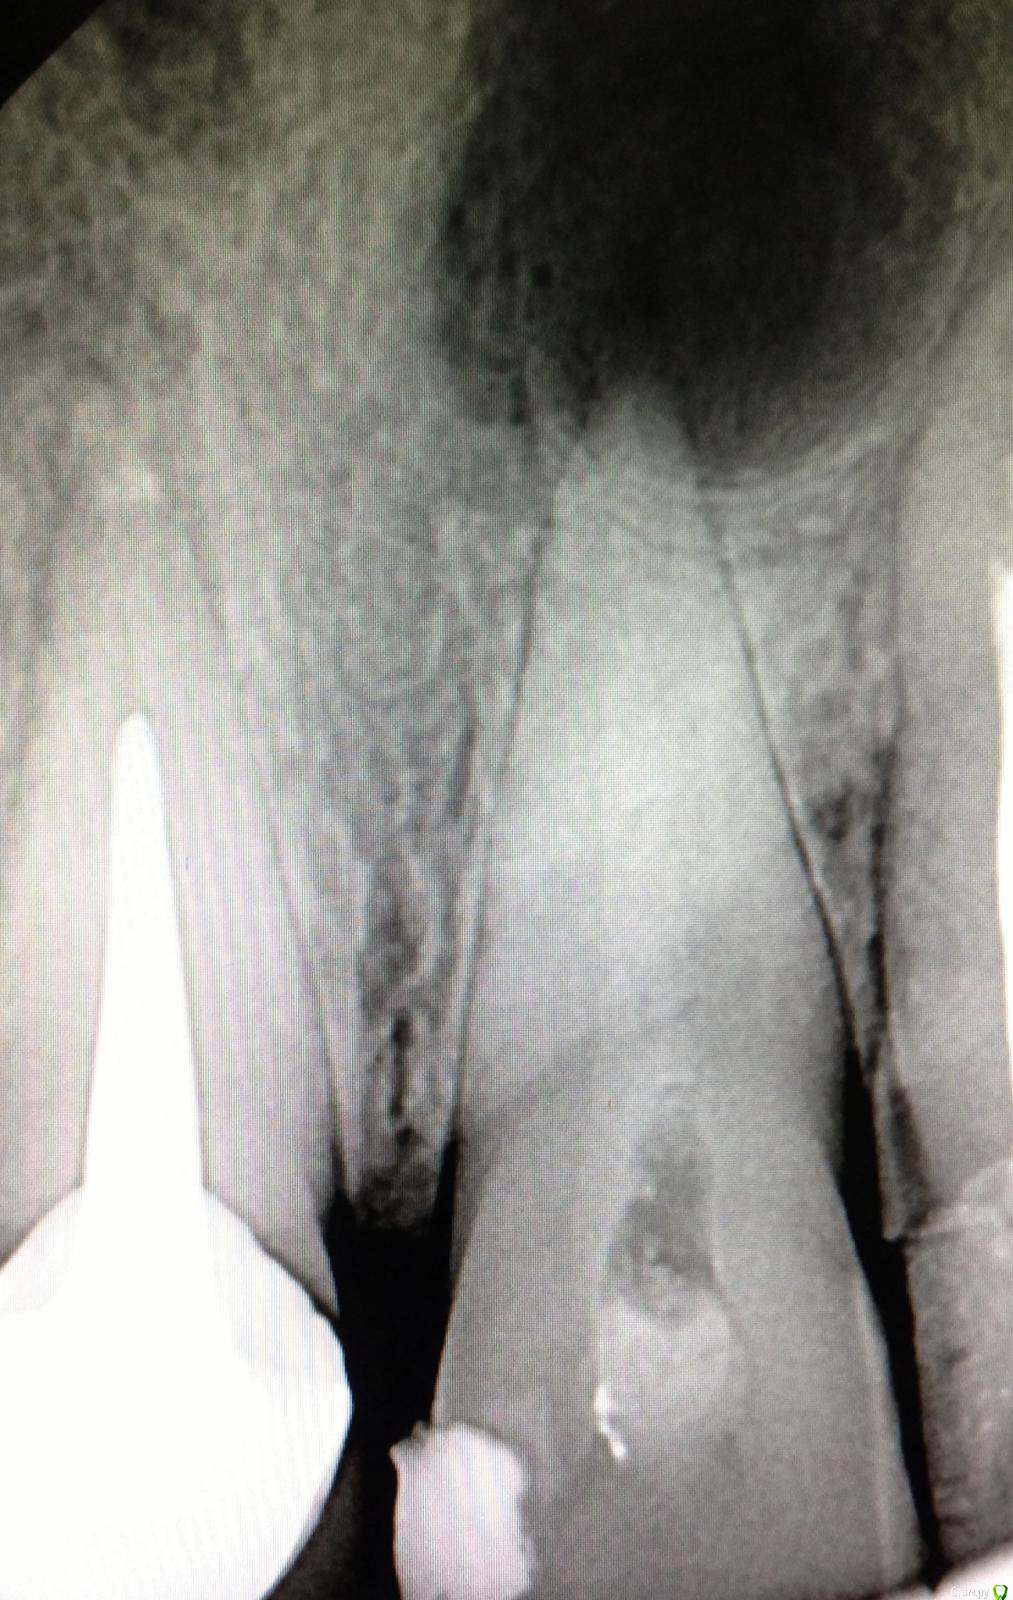

Natalia :) Опубликовано 16 декабря, 2014 Поделиться Опубликовано 16 декабря, 2014 Так. Только стоило отвлечься- понакидали снимков своих. НегодяиСорри,я парочку выложу,потому что мне срочно нужно понять,что я не так делаю...Принимаю самую жесткую критику,потому что и сама все вижу,сравнивая свои с вашими красивыми картинками)работаю первый год,но хочется,конечно, сразу хорошо работать...Про спредеры и гутту поняла,завтра буду выполнять рекомендацию,спасибо)На этом снимке не понимаю,что за хрень нечеткая по стенкам к.к?и тут хрень какая-то пористая,еще и в апикальной трети(здесь полость раскрыта ужасно,знаю,плохой обзор был.Спасибо за внимание 3 Ссылка на комментарий